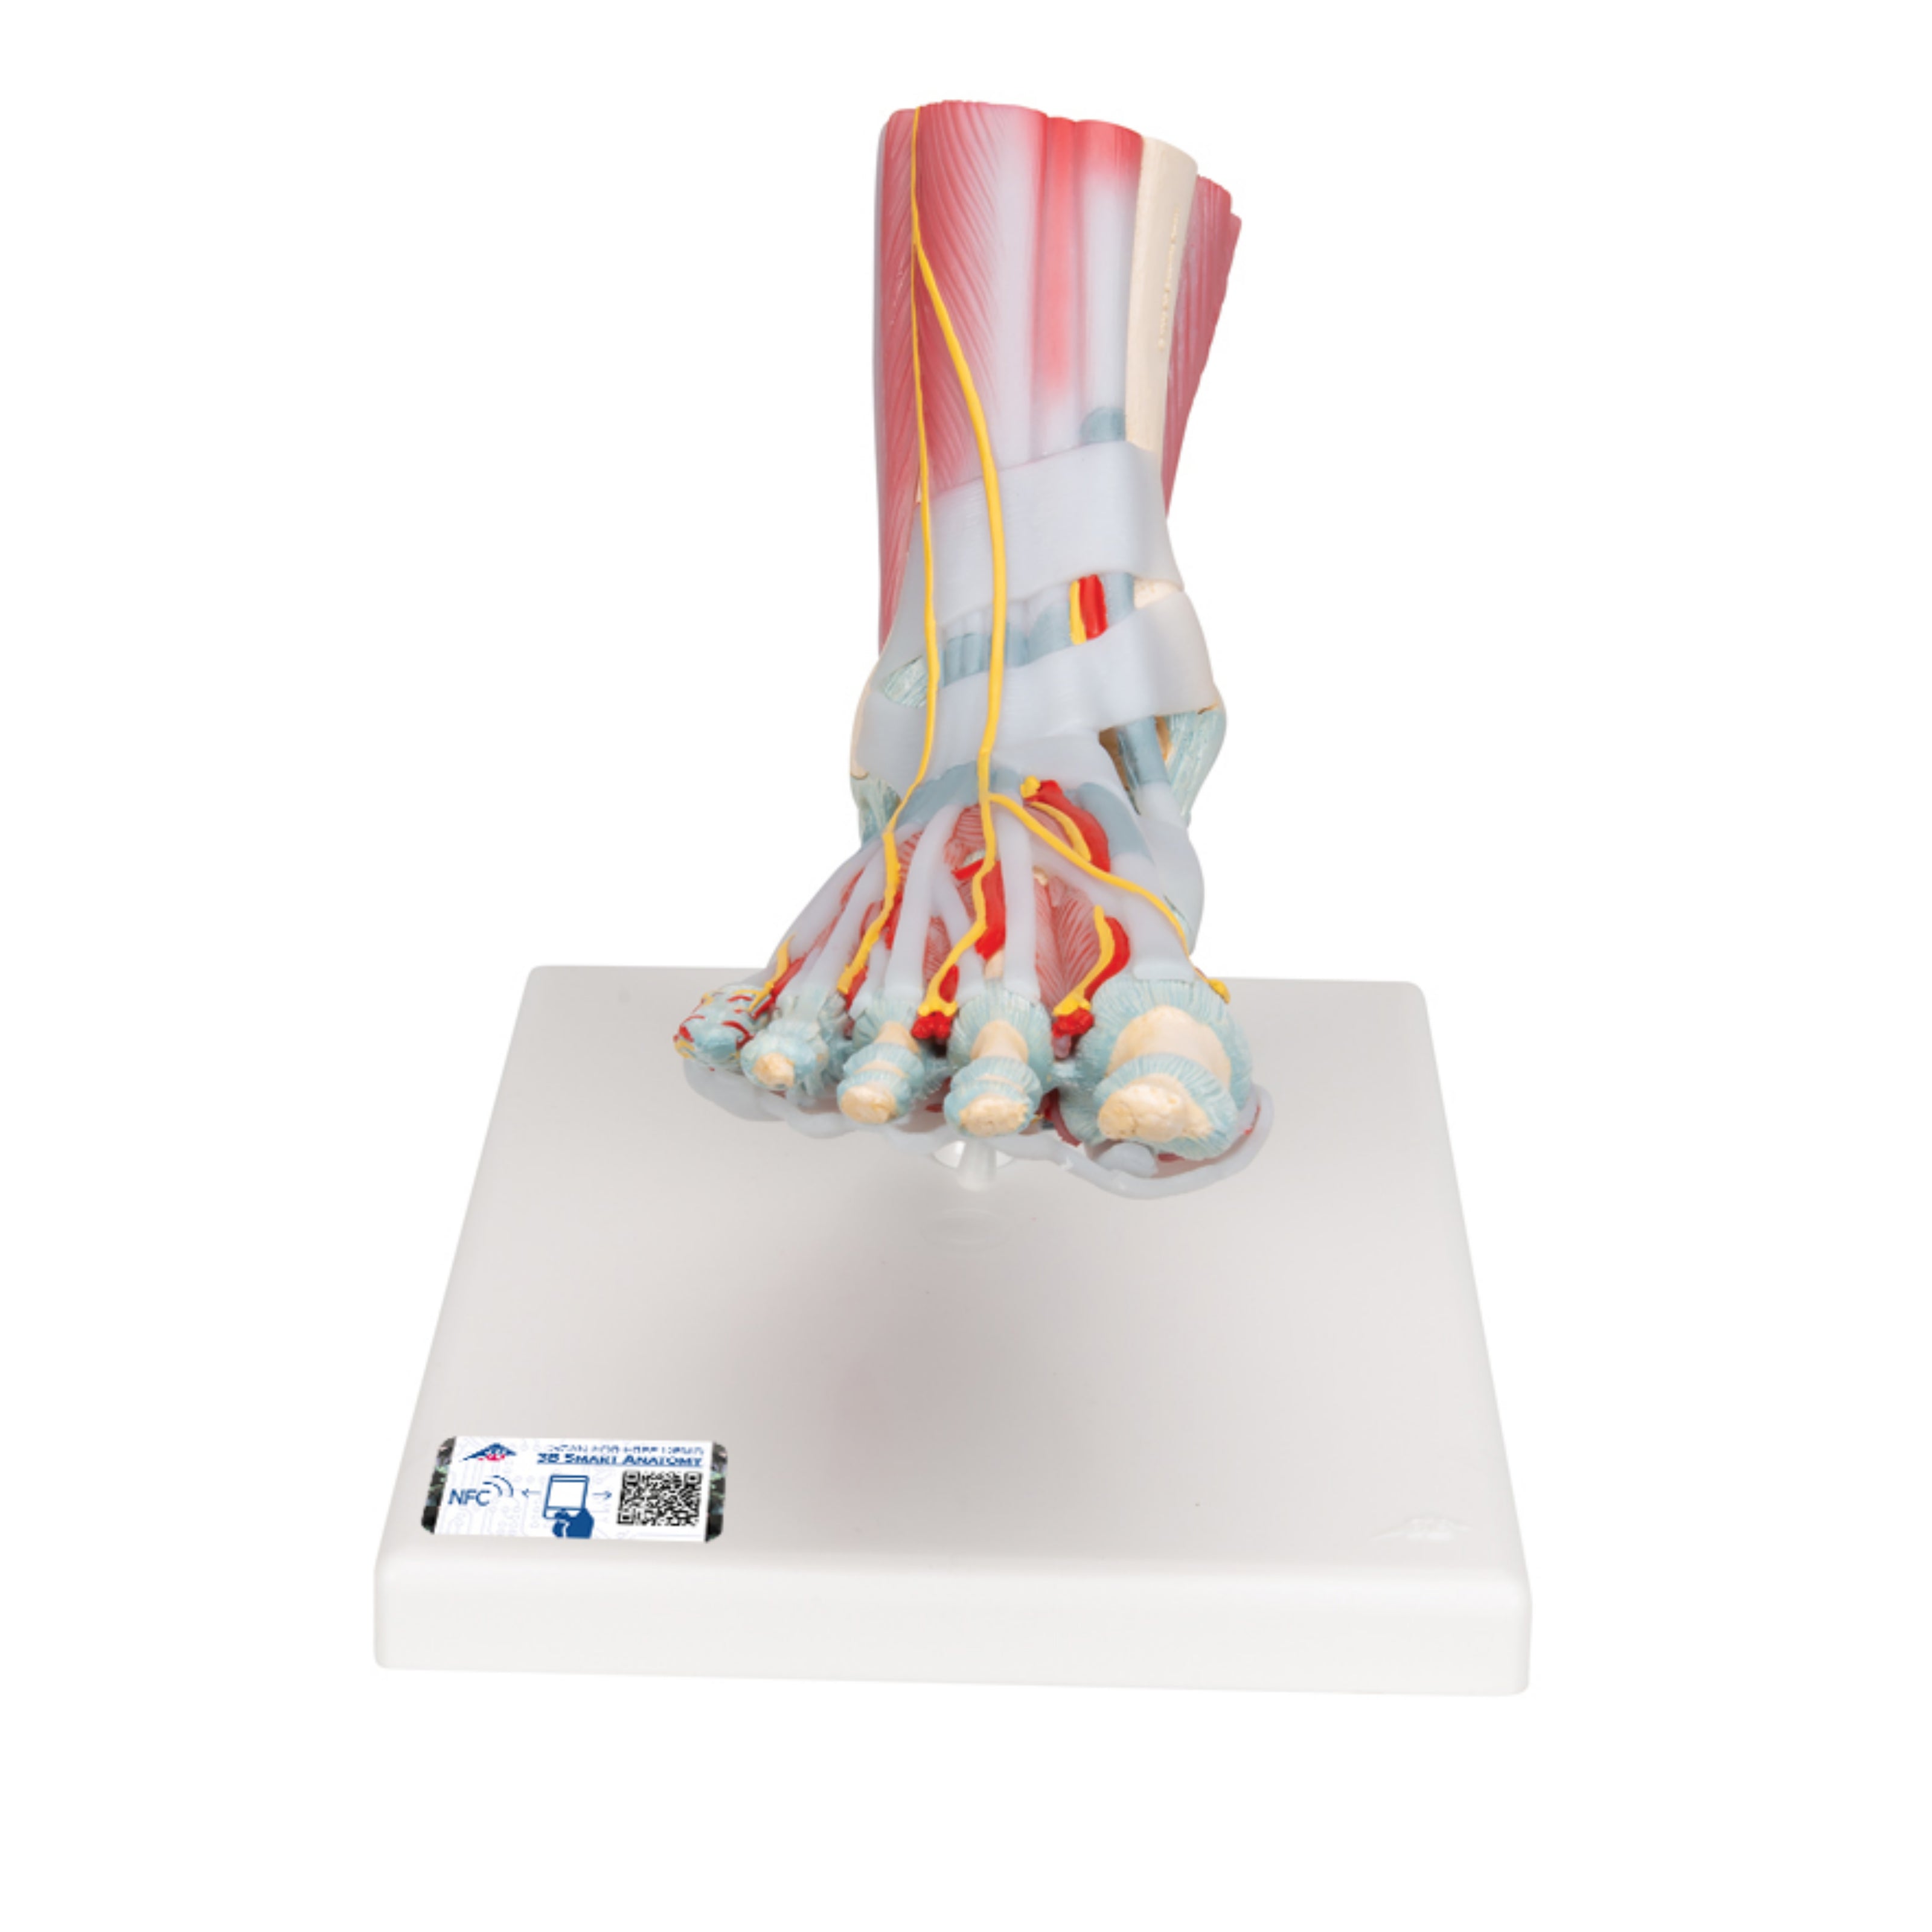

3B Scientific

Modelo Anatómico del Esqueleto del Pie con Ligamentos y Músculos - 3B Smart Anatomy

Precio de venta$14,896.38